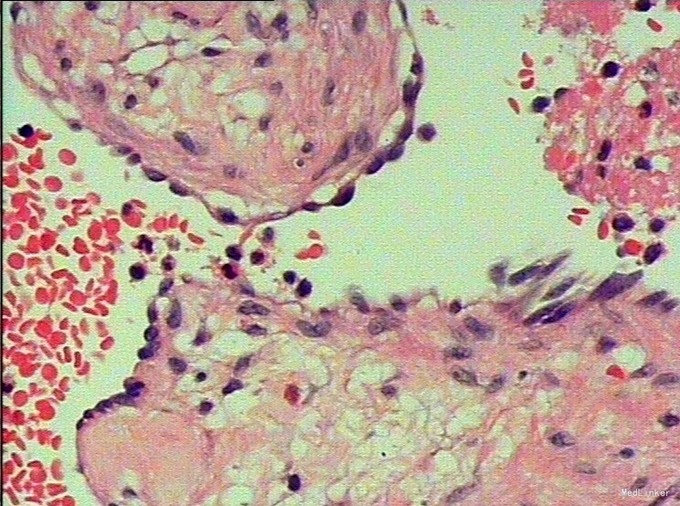

随访:(肝S4/5段血管瘤)海绵状血管瘤;周围肝组织小叶结构保存,肝细胞胞浆内见较多胆色素颗粒;“切缘”未见肿瘤。 讨论:肝海绵状血管瘤是肝脏最常见的良性肿瘤,约占肝脏良性肿瘤的84%,一般无临床症状,常为体检中发现。海绵状血管瘤内的血窦和血窦内缓慢流动的血液形成MRI颇具特征性表现,T2WI呈均匀高信号,随着回波时间延长,信号强度增高,临床上称为灯泡征。增强扫描呈“快进慢出”表现,即动脉期边缘结节样明显强化,门脉期及静脉期强化逐渐向中央扩展。影像学表现较具特征性,诊断不难。